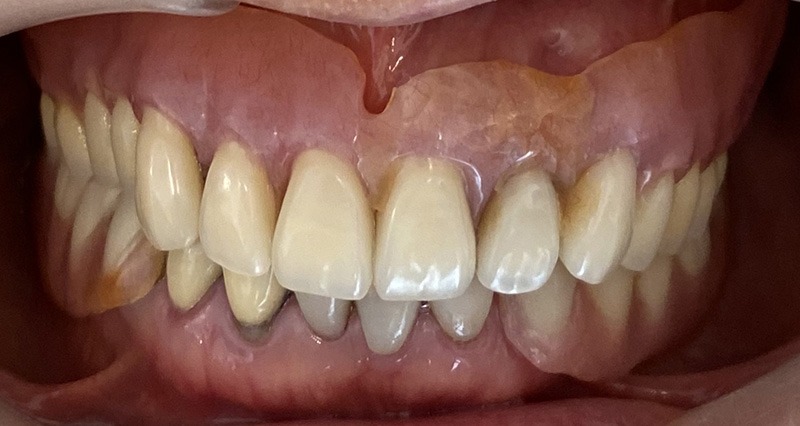

口腔内(正面)

Before

After

最終補綴装置は上下フルジルコニア上部構造で、傷が付かない、臭いが付かない最も整体親和性の高い素材です。当クリニックでは万が一の破折に備え全てのジルコニアにスペア(人工歯タイプ)を用意し、なるべく患者様にご迷惑がかからない治療を行なっております。